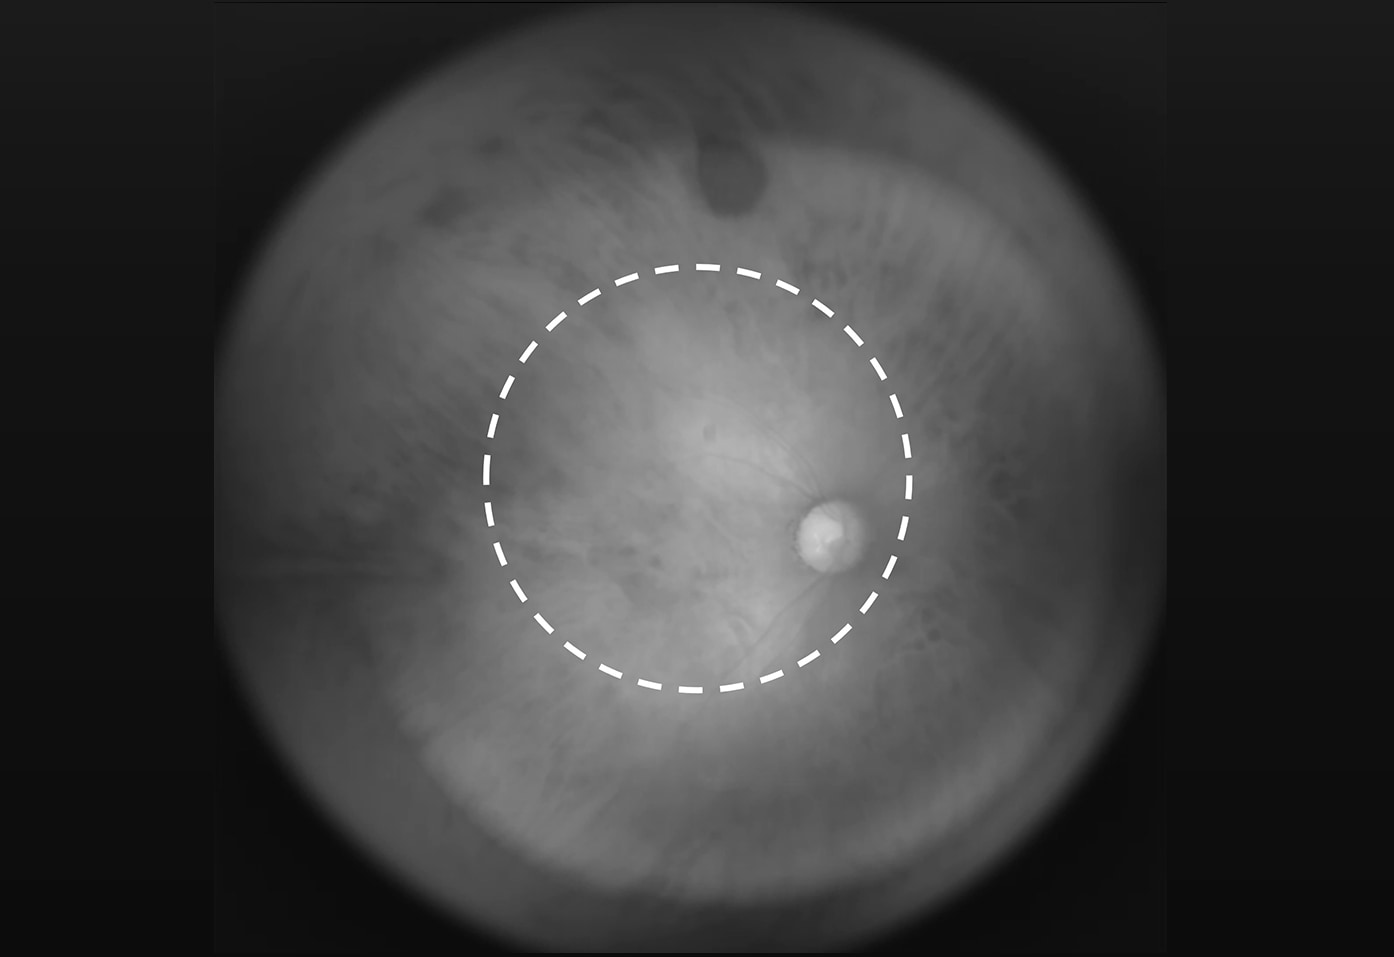

• Fundus camera are used for early detection of frequent causes in Japan of blindness such as glaucoma, retinitis pigmentosa and diabetic retinopathy. Although wider view angle is necessary for eye fundus imaging and examination, existing cameras currently used for medical examination have viewing angle of 60°which detects only part of eye fundus. There are difficulties in designing a lens for clear photography of a concave sphere such as the fundus, and projecting light through the lens to the fundus. Tamron has specifically designed and completed a prototype of hyper-wide-angle lens optimized for fundus photography. The lens was installed into near-infrared fundus camera developed by Nara Institute of Science and Technology and approximately 180° of hyper-wide viewing angle photographing was achieved. Without mydriatic (eye drop) used to dilate the pupils, a wide field of eye fundus image can be acquired.